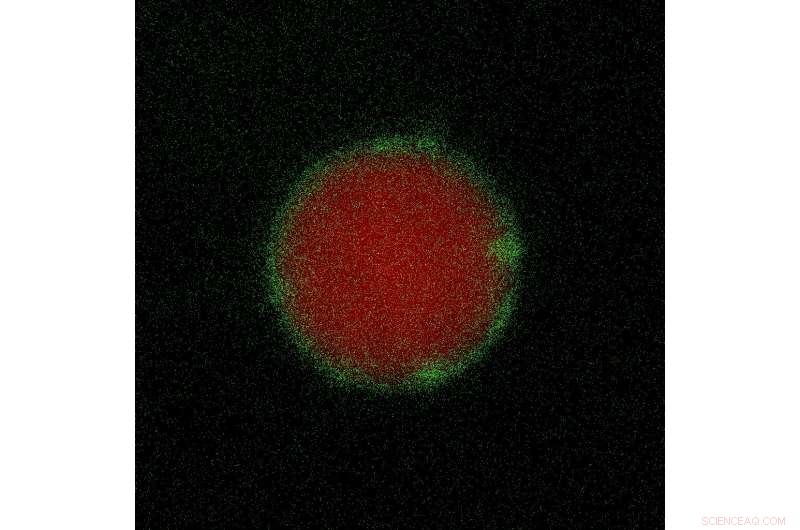

Delivering a protein (red fluorescence) to mice testes with a fibroin nanoparticle-encapsulated cationic lipid complex (green) restored male fertility. Credit: Adapted from ACS Nano 2020, DOI: 10.1021/acsnano.0c04936

The researchers developed a delivery system called Fibroplex, which consisted of spherical nanoparticles made of silk fibroin and a coating of lipids. They loaded PIN1 into Fibroplex, and showed that the particles appeared safe and didn't show signs of toxicity or testicular damage in mice. When the team injected the PIN1-loaded Fibroplex into the testes of young mice with PIN1 deletions, the treatment restored nearly normal PIN1 levels and sperm stem cell numbers and repaired the BTB. Treated mice had normal testicular weight and size and about 50% of the sperm count of wild-type mice. Until about 5 months after treatment, when the protein degraded, the PIN1-Fibroplex-treated mice fathered a similar number of pups as wild-type mice, whereas untreated mice with PIN1 deletions remained infertile. This is the first demonstration of direct delivery of proteins into the testis to treat male infertility, the researchers say.